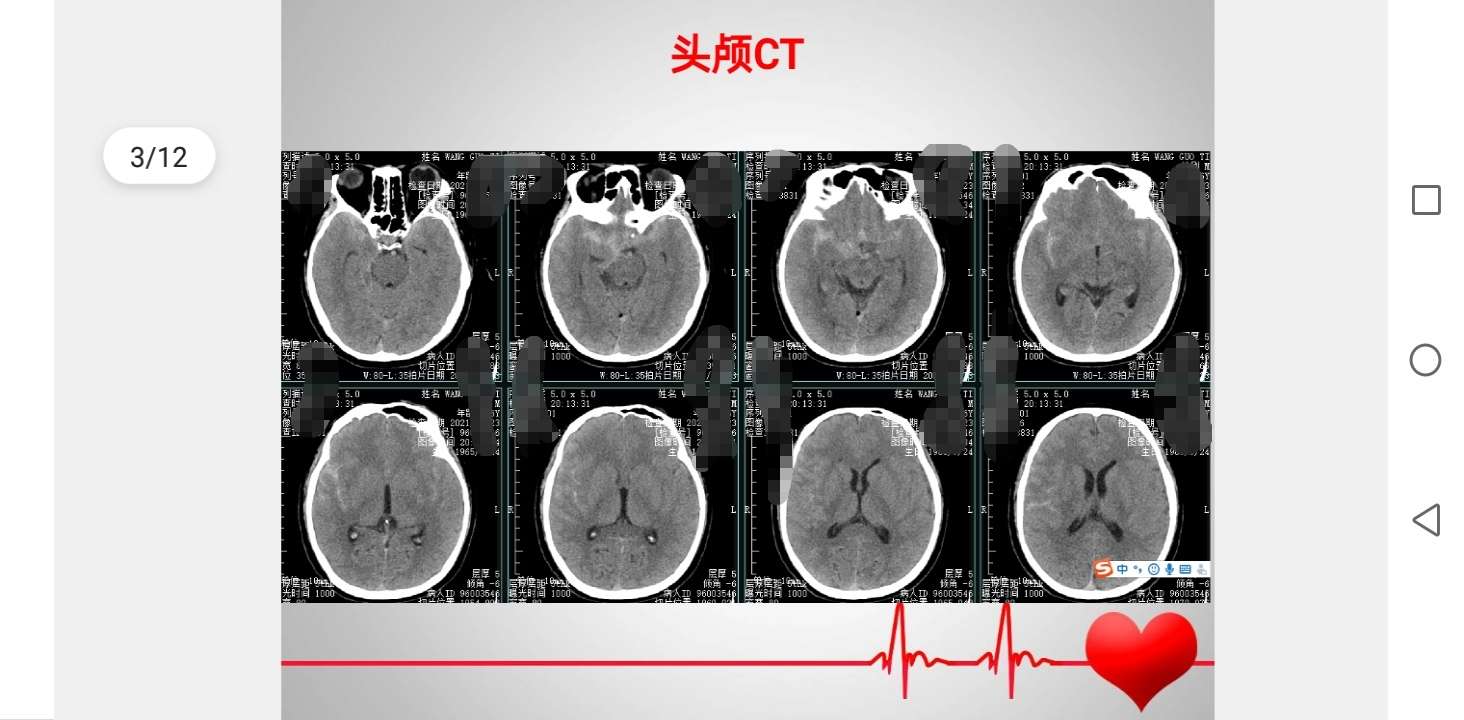

50岁男性患者,突发头疼一天入院,头颅CT检查提示蛛网膜下腔出血